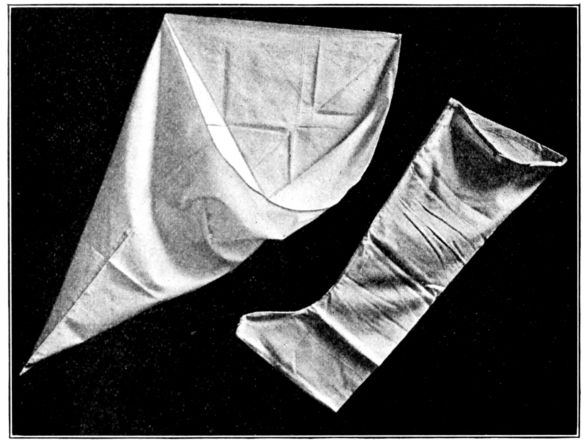

| 110. | Two types of leggings for obstetrical use | 304 |